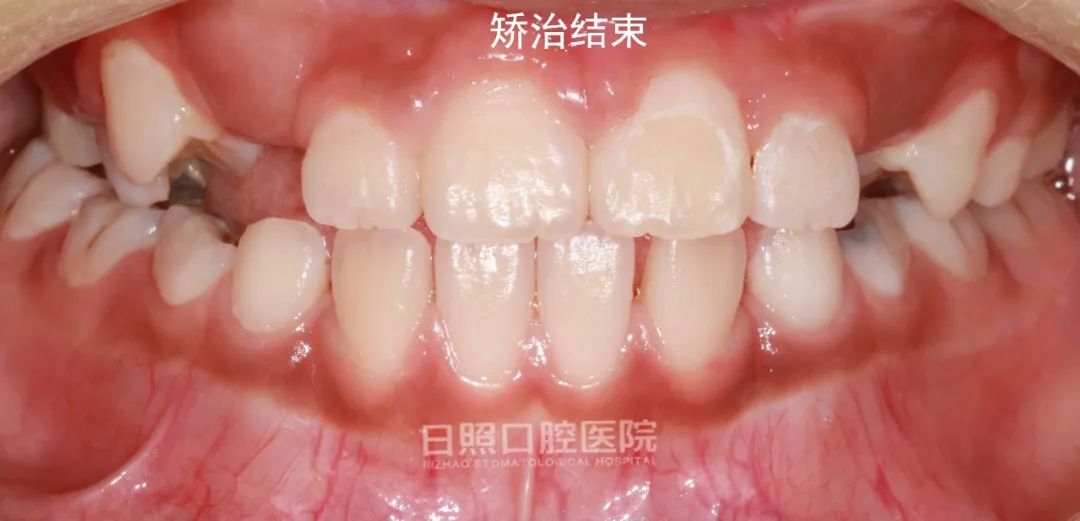

手术开窗和正畸牵引的工作做完以后,就是等待牙齿逐渐萌出,接下来的几张图片就是2.5个月、5个月、7个月、10个月直到矫治后的图片,大家一起来见证一下”奇迹“吧!

矫治过程结束了,再拍一张全景牙片看一下吧,倒置埋伏阻生牙“迷途知返”,乖乖地呆在了正确的位置。